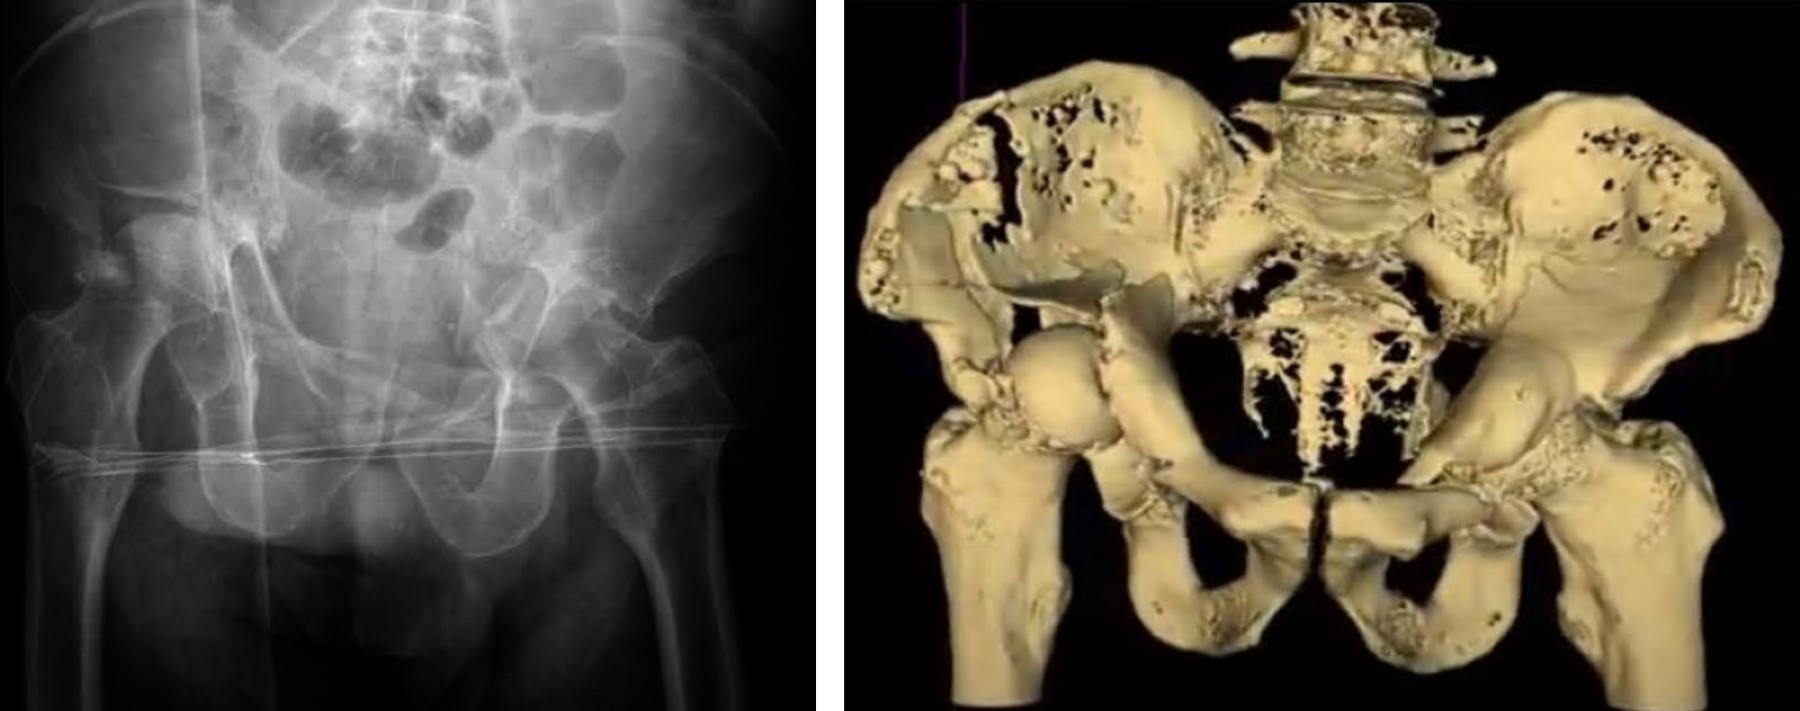

De primera instancia, se llevó a cabo la cirugía de la hemipelvis izquierda dado que a nivel radiográfico presentaba mayor protrusión pélvica y no era deseable que un hematoma en fase de callo blando pudiera generar complicaciones al momento de la extracción de la cabeza femoral (lesiones vasculares, sangrado intraoperatorio). Se retiró la tracción supracondílea. Se colocó al paciente en decúbito lateral derecho, realizándose abordaje posterolateral de Moore con colocación de autoinjerto de la cabeza femoral en el trasfondo acetabular (foco de fractura). Seguidamente, implantación de anillo antiprotrusivo (Burch SchneiderTM Reinforcement Cage, Zimmer Biomet) anclado a isquion e ilion (Figura 2). Previa implantación del anillo, se requirió realizar disección de musculatura glútea (glúteo menor y medio) para alojar correctamente la pestaña superior ilíaca del anillo mediante tornillos corticales. La pestaña medial isquiática del anillo también se ancló mediante tornillos. Se realizó comprobación bajo control de escopía de correcta implantación. Posteriormente, se insertó cotilo de doble movilidad cementado al anillo antiprotrusivo y después se llevó a cabo la implantación del vástago femoral no cementado. Tras finalizar la colocación de los componentes, se procedió al cierre capsular y de musculatura pelvitrocantérica mediante puntos transóseos trocantéricos.

La cirugía de la hemipelvis derecha se llevó a cabo siete días después de la primera. Se colocó al paciente en decúbito lateral izquierdo. Para abordar la fractura longitudinal de pala ilíaca se realizó la primera ventana lateral del abordaje ilioinguinal. Se sintetizó con placa anatómica de seis agujeros. Posteriormente, se realizó el mismo procedimiento que la cirugía previa, usando anillo antiprotrusivo con cotilo de doble movilidad cementado y vástago femoral no cementado.

Durante el seguimiento del paciente, a los 12 meses de la intervención ya realizaba carga completa con la ayuda de un bastón, con una puntuación de Harris hip score (HHS) de 79 en cadera izquierda y 77 en cadera derecha; y una puntuación de 12 en la escala de WOMAC. No ha presentado ninguna complicación postoperatoria hasta el momento (Figura 2). El paciente clínicamente se encuentra satisfecho, refiere molestias ocasionales y una leve cojera de predominio derecho. Presenta balance articular completo a la exploración y no refiere haber tenido ningún episodio de inestabilidad desde la cirugía.

Figura 2